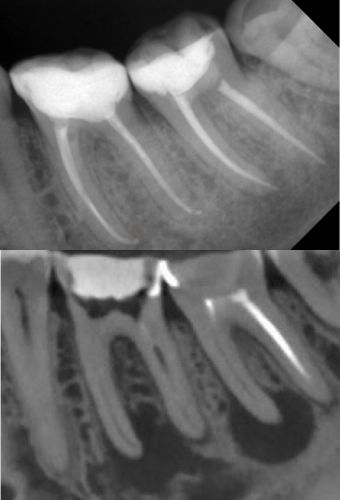

эндодонтическое лечение